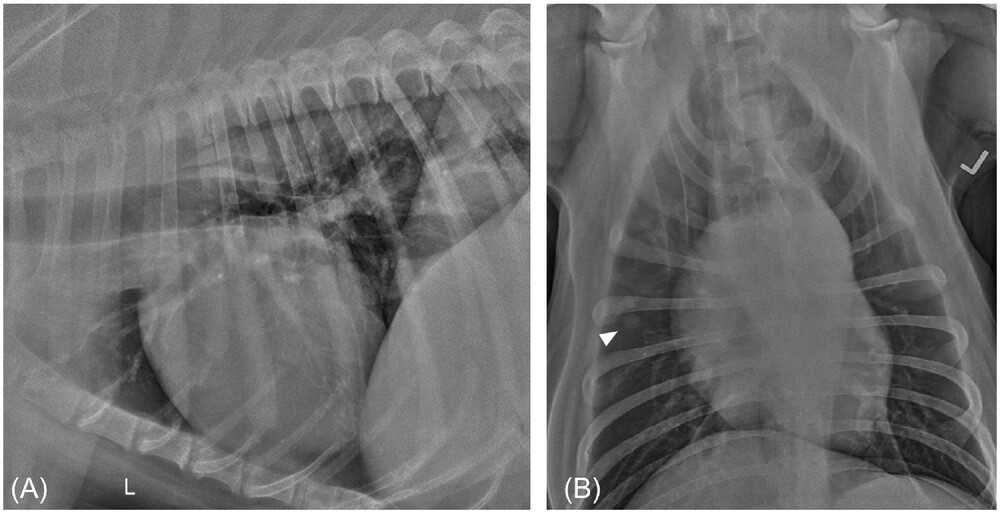

Machine learning analysis of intestinal disorders in cats

VRU 2023 64(5): 890-903